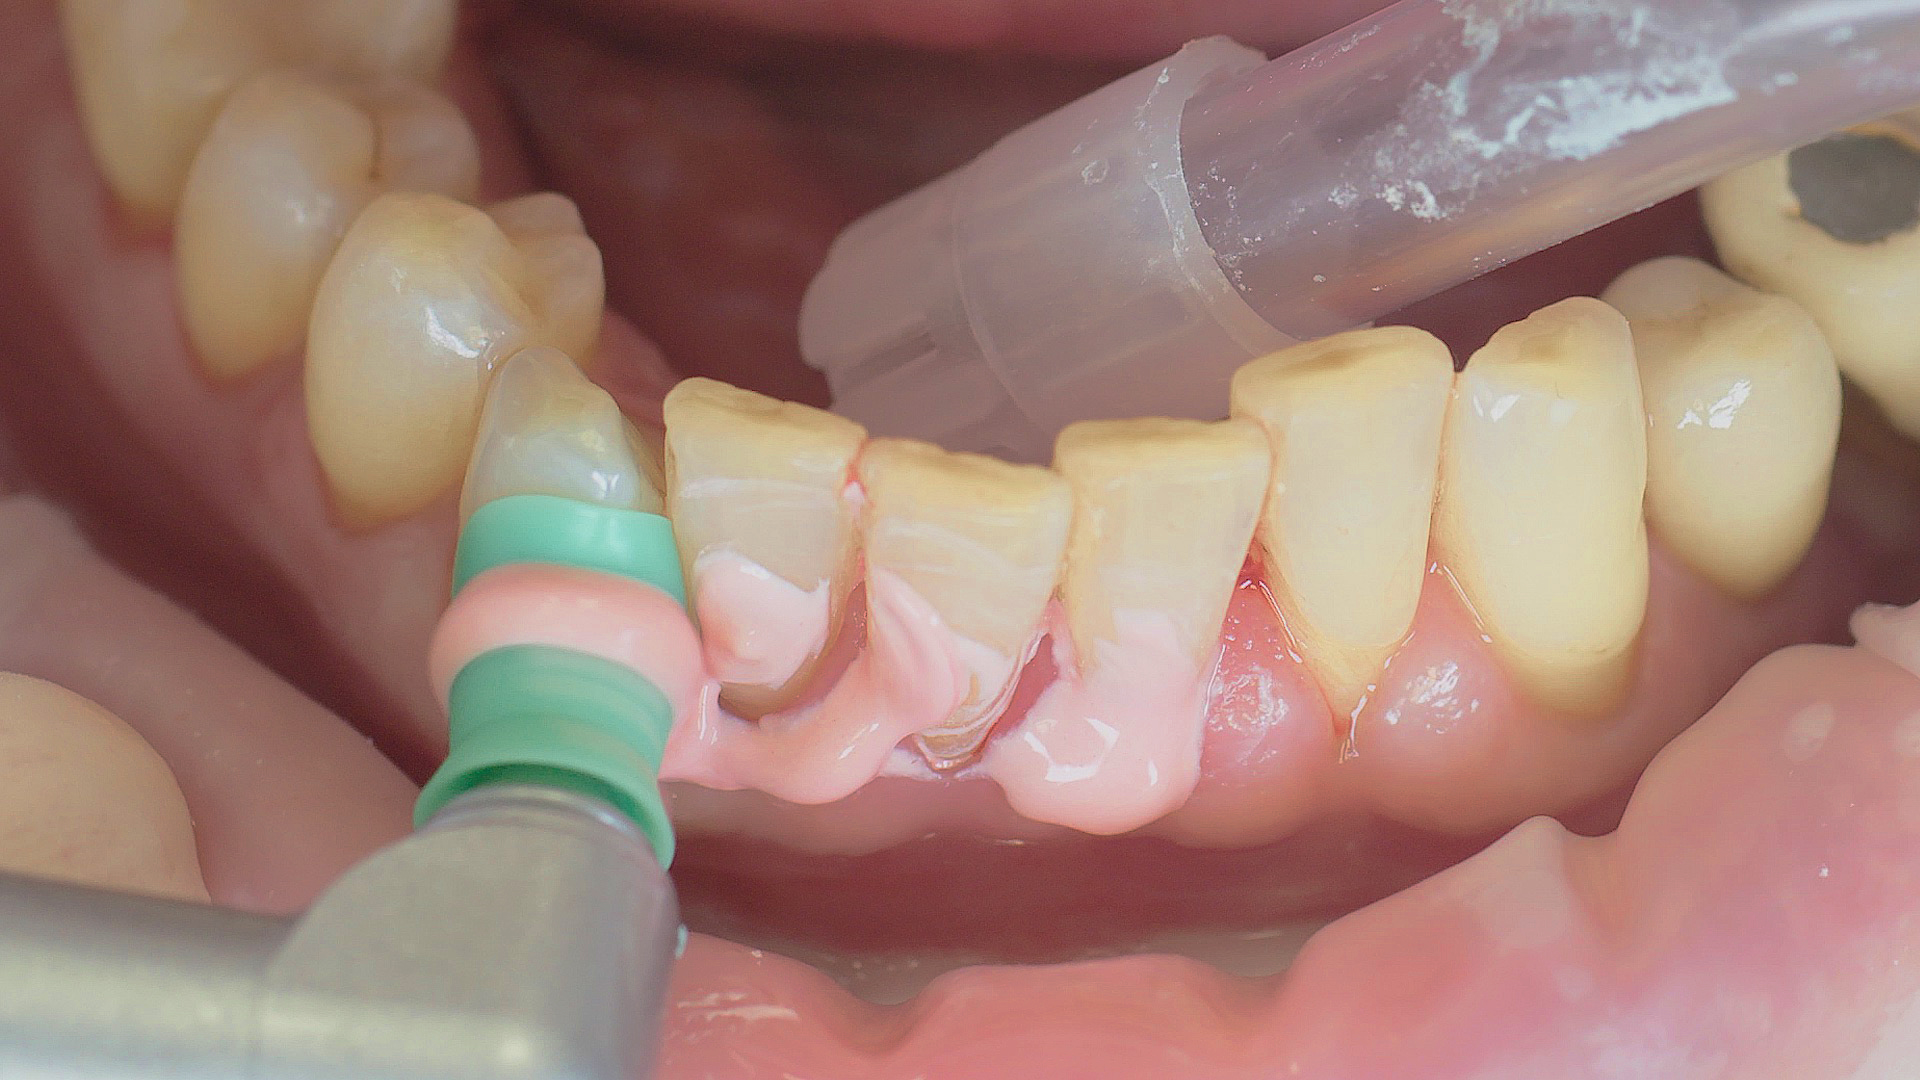

Every dental examination is based on a detailed medical history combined with targeted diagnostics con- taining as much detail as possible: The dentist records systemic risk factors such as diabetes or smoking and identifies any potential increased tendency to inflammation.[3] Hard and soft tissues are examined and periodontal pockets are probed in a screening test according to PSR (Periodontal Screening and Recording). In case of abnormal findings, the periodontal status is then re- corded and therapy is initiated where necessary. This treatment begins with professional biofilm management, by using, for example, rotary cups and polishing com pounds (Fig. 1), and comprehensive instructions in oral hygiene. Sonic or ultrasonic systems remain an effective alternative or supplement to manual instruments for sub- gingival debridement and biofilm management (presentation by Prof. Dr Ulrich Schlagenhauf; Fig. 2). Supplementary use of photodynamic therapy, air polishing or local and systemic antibiotics is not adequately documented (Prof. Dr Sema Hakki).[4] According to Dr Sergio Bizzarro, improved biomarker diagnostics may lead to an increase in customised patient therapy in the future.

Good individual oral hygiene and professional biofilm management

Fig. 1: Good individual oral hygiene and professional biofilm management, e.g. with cups and brushes, helps support periodontal and peri-implant health.